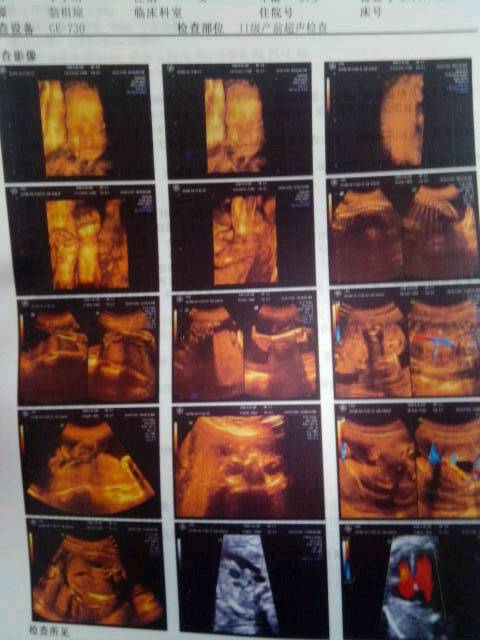

有没好心医生帮忙看看这些图分别照了小孩的哪些部位啊?前五幅知道是哪里,后面就不知道了,忘记问医生了

你好,后面的都是宝宝的脏器,最后一个是心脏,亲只要看报告就可以了,只要正常就好。

这是做的四维彩超吧,后面都是照的孩子内脏